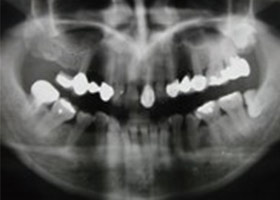

治療前全口X光片、口內正面照片。

假牙拆除前的X光片,可看出假牙已不密合。